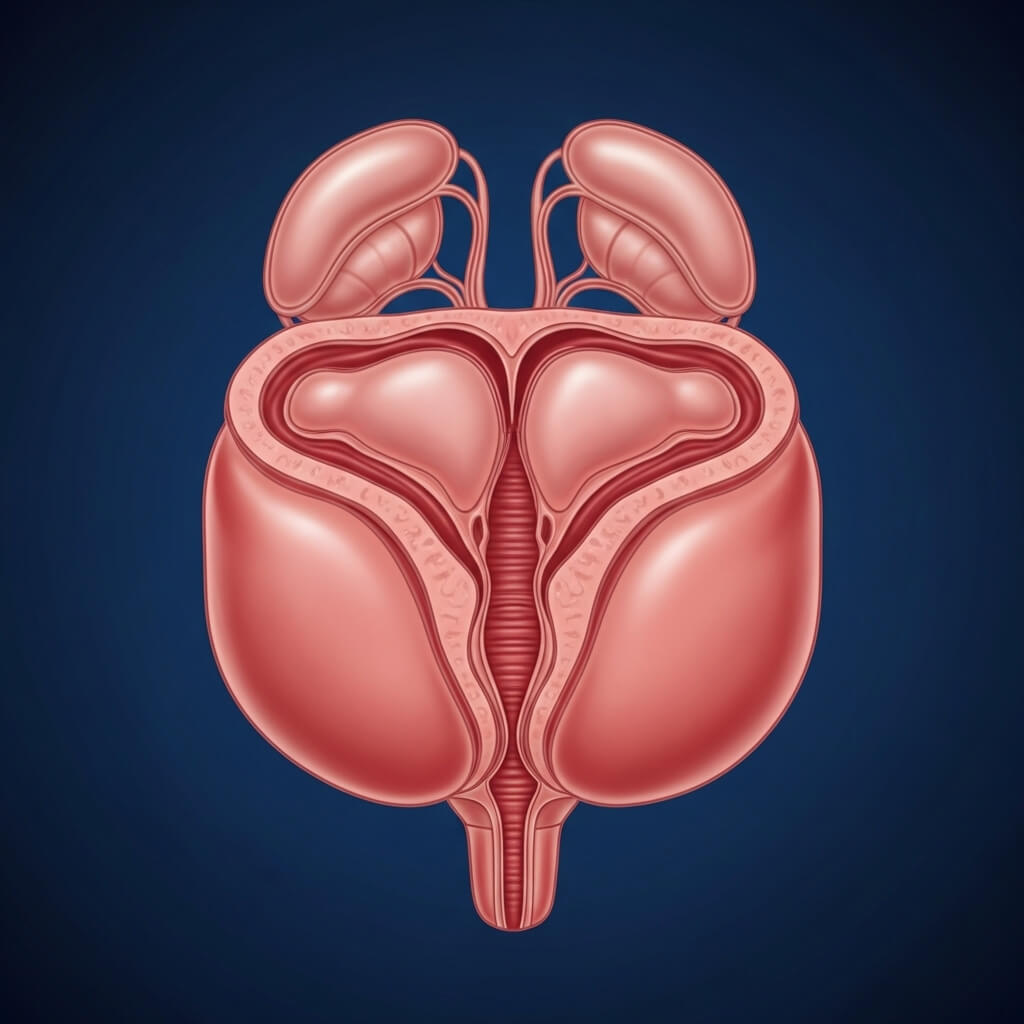

ENLARGED PROSTATE?

The Silent battle Inside Your Body... And the Breakthrough

That Ends It

For years, an enlarged prostate slowly squeezes your bladder like a vice - making it

harder to pee, harder to feel like a man.

STAGE 01

CHAOS

Severe inflamation. Zero flow. Constant pressure.

Doctors prescribe pills...or schedule surgery.

STAGE 02

DETOX

After 7 days using the ritual: swelling begins to drop

Bladder pressure eases. Nightmare trips reduce.

STAGE 03

REGENERATION

After 2 weeks: urine stream improves, urgency fades.

Your body is flushing the toxic gunk out naturally.

STAGE 04

CONTROL RESTORED

After 30 days: your prostate is balancead, healthy, and strong.

No pills. No surgeries. Just one natural ritual that changed everithing.